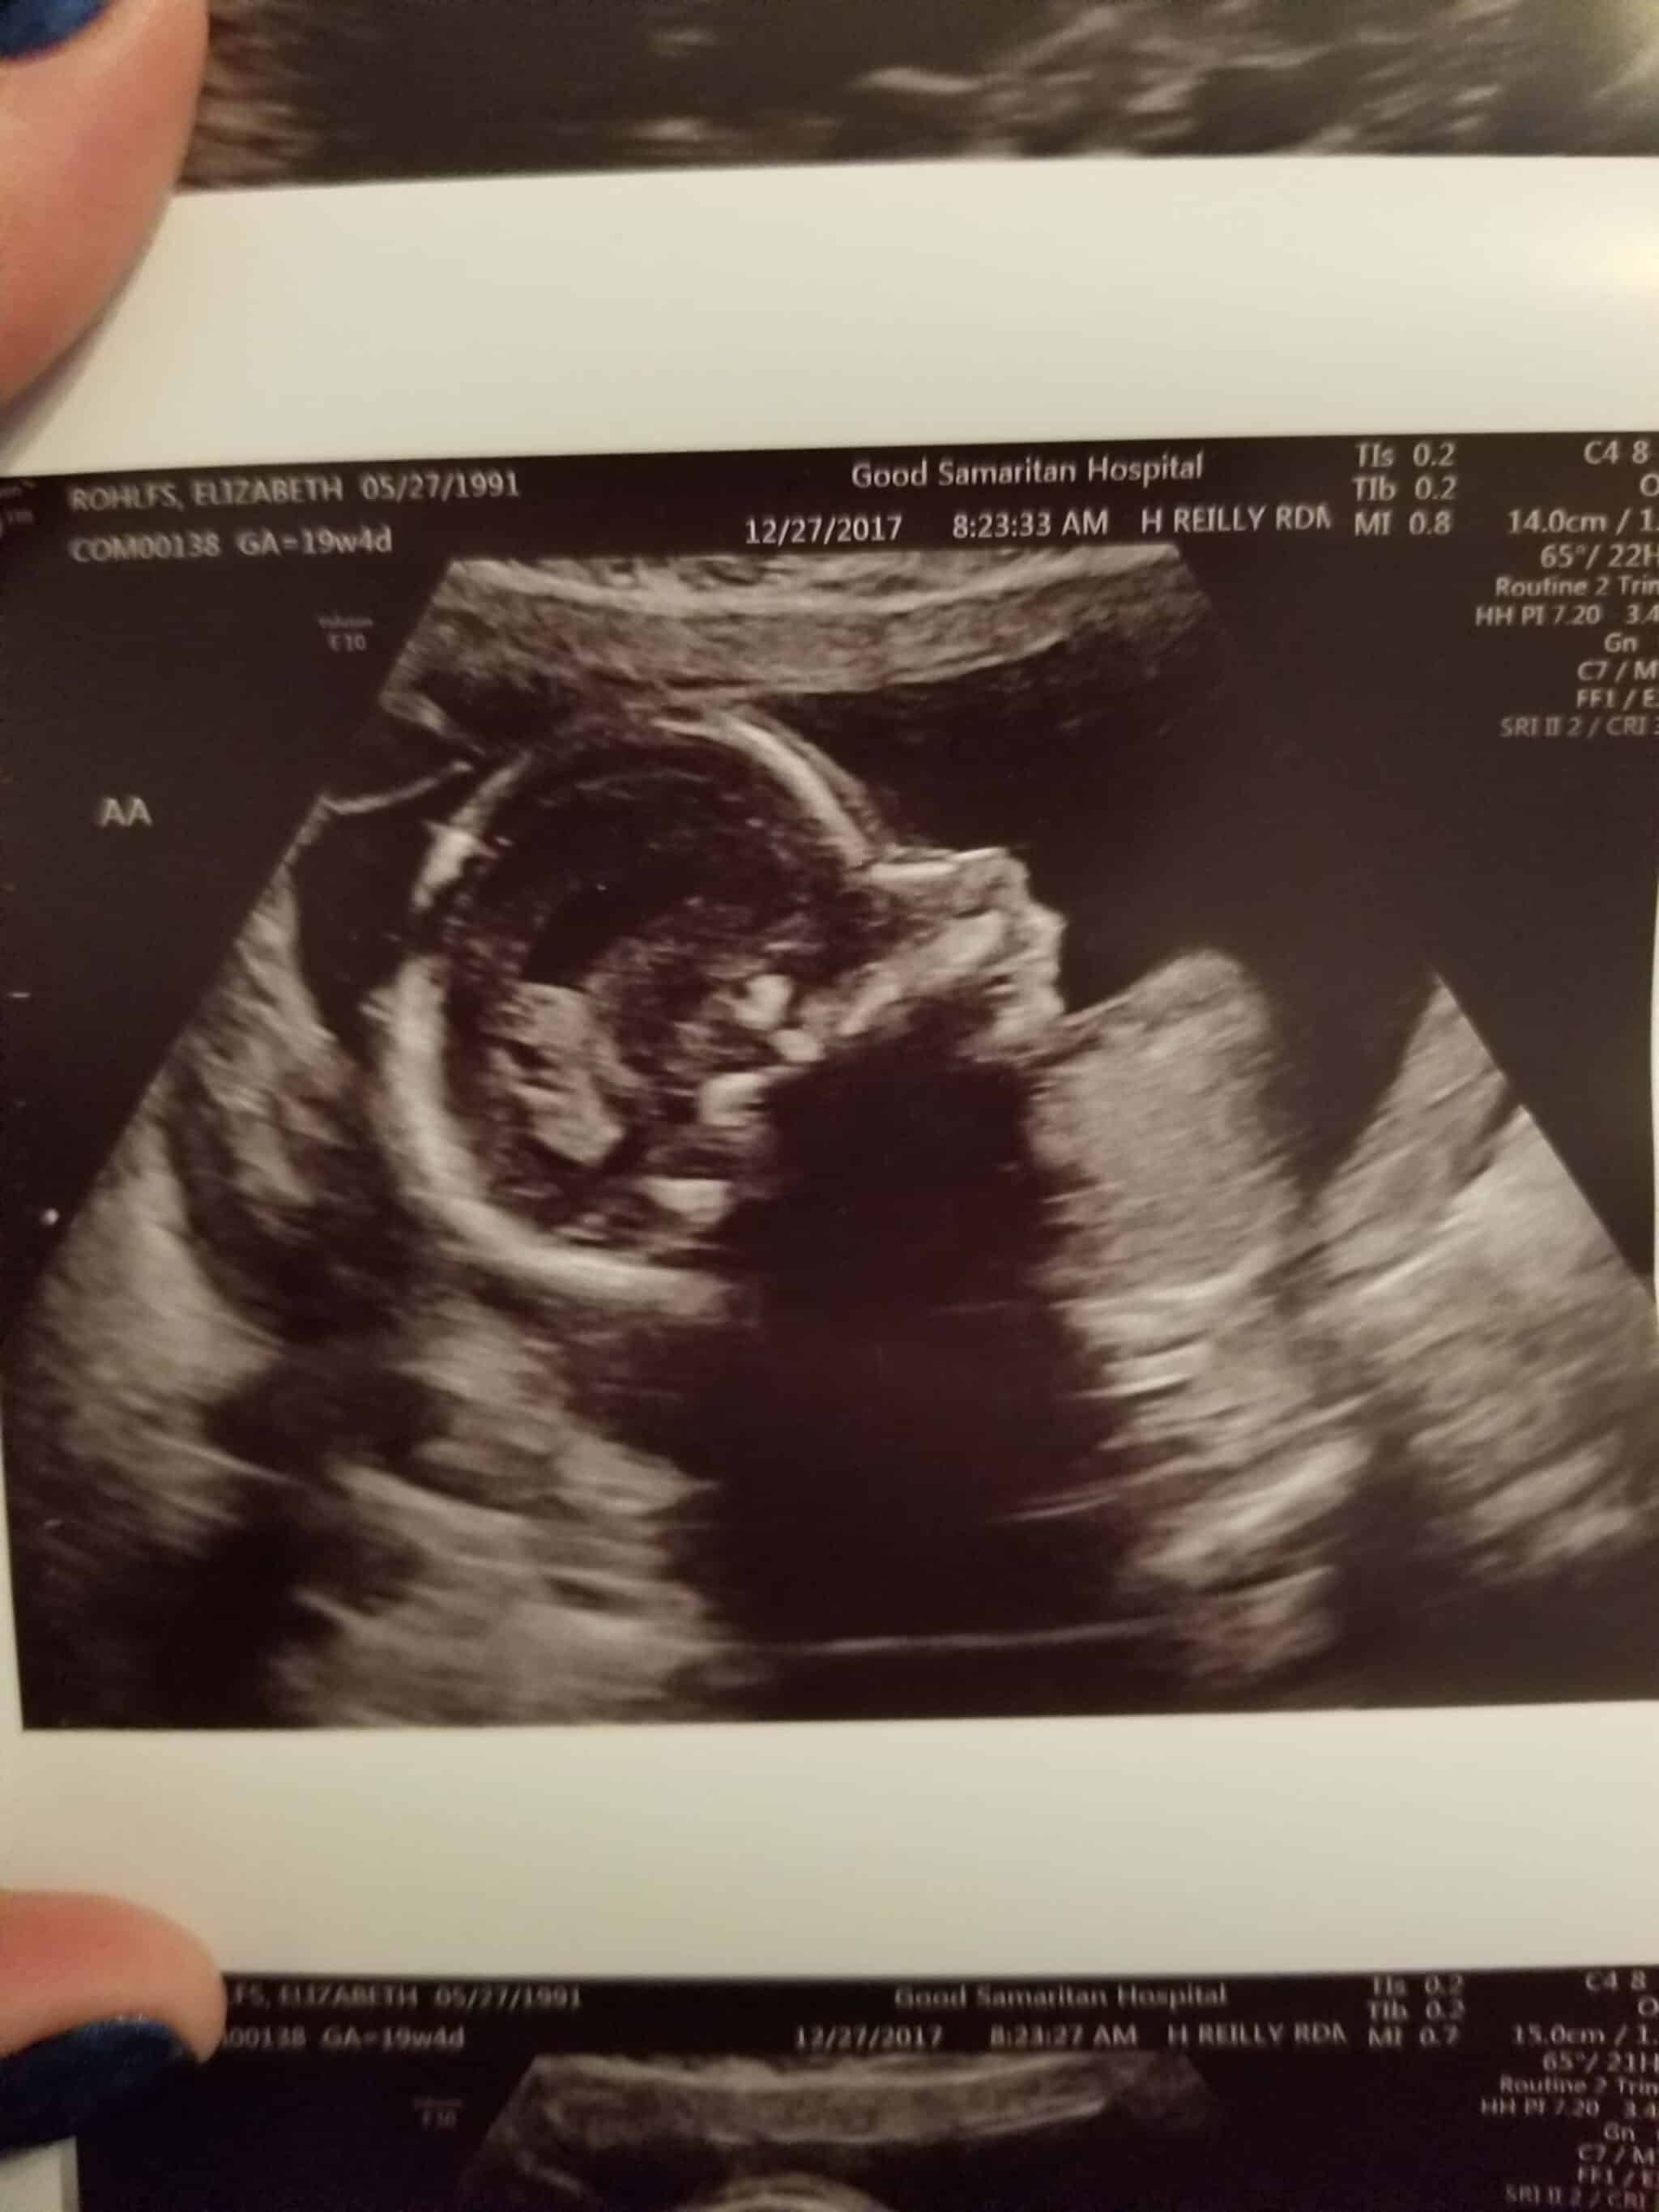

Ultrasound Photos at 19 Weeks Pregnant With Twins